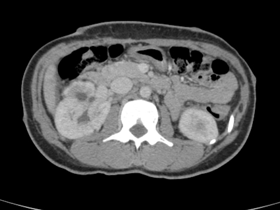

Imagens associadas à LAM e à esclerose tuberosa

Angiomiolipoma renal à direita

Angiomiolipomas renais